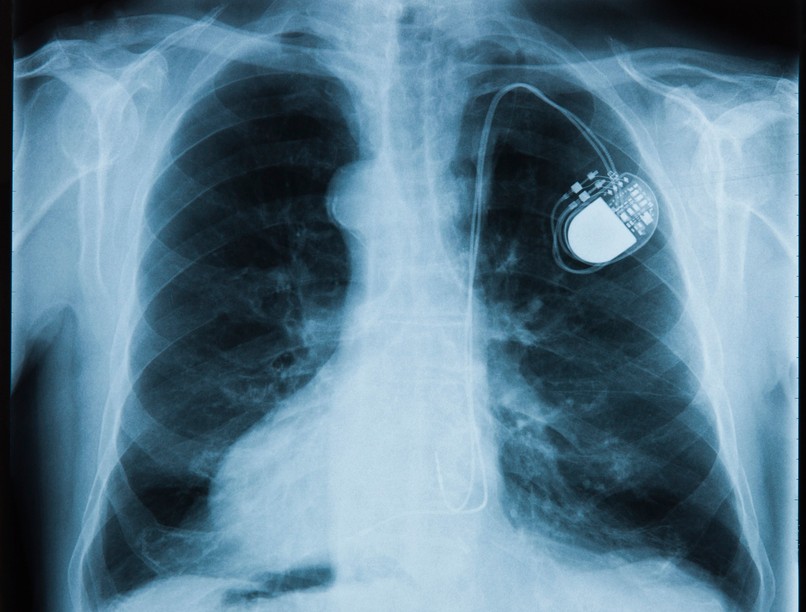

Bizonyos szívbetegségek, kóros állapotok esetén a legmegfelelőbb eljárás, ha a páciensnek pacemakert vagy defibrillátort ültetnek be.

A pacemaker tulajdonképpen egy szívritmus-szabályozó készülék, amely ellenőrzi a szívritmust, és ha túl lassúnak találja azt, elektromos impulzusok leadásával hatékonyabb munkára készteti a szívet. A korszerű defibrillátor ennél egy kicsit összetettebb feladatokra is képes: a túl lassú szívverés serkentését túl a felgyorsult szívritmust is képes lassítani, sőt, ha szükséges, az életveszélyes kamrafibrilláció esetén lead egy nagy energiájú impulzust, vagyis defibrillál.

Mindkét készüléket kisebb műtét keretében ültetik be. Jellemzően nem altatásban, hanem érzéstelenítés mellett történik a beavatkozás. A legtöbb esetben a készülék telepét a kulcscsont alá, legtöbbször baloldalt ültetik be a bőr alatti zsírszövetbe. Innen egy vénán keresztül vezetnek fel 2, vagy 3 elektródavezetéket a szívbe, amelyeket összekötnek a vezérlőteleppel, egy kis fémdobozzal. Az elektródákat az adott szívritmuszavarnak megfelelően a szív jobb kamrájában, jobb pitvarában, biventrikuláris pacemaker esetében emellett a szív egyik oldalvénájában helyezik el.